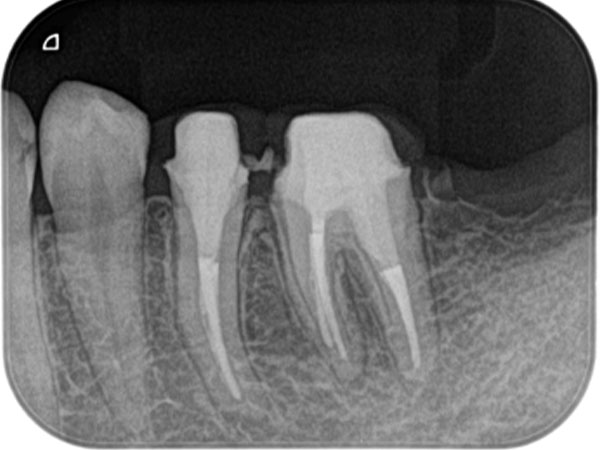

下の写真をご覧ください。歯の中に見える黒い部分が「根管」です。根管の形は複雑で、患者さんひとりひとりによって異なります。しかも細いところは直径1mmもありません。こんなに狭くて複雑な根管から、感染部位を正確に取り除くというのは困難を極めます。

複雑な根管を治療するには、事前の画像診断で根管の形状を可視化することが重要です。多くの歯科医院では、画像診断に「2次元」のレントゲンが用いられますが、レントゲンでは初期の患部を見つけにくい上に、根管の複雑な形状をしっかり可視化するほどの力はありません。

そこで、当院では3次元で撮影ができる「CT」を利用します。CTはあごの骨の中を立体的に可視化するので、レントゲンには写らない患部の様子までがしっかりわかります。日本国内の歯科医院での、CTの普及率は5〜10%程度と言われています。